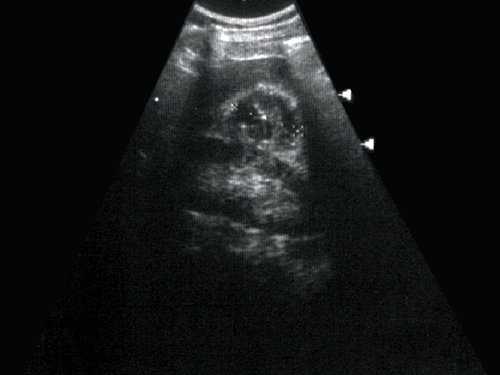

(Слева) УЗИ, продольная плоскость сканирования, правая почка: скопление множества кист. Каждая киста имеет типичный доброкачественный вид.

(Справа) МРТ, Т2-ВИ, коронарная проекция: у этою же пациента выявлено скопление кист в нижнем полюсе правой почки. Отсутствие капсулы позволяет предположить локализованную кистозную болезнь почек. Обратите внимание на рассеянные кисты левой почки.